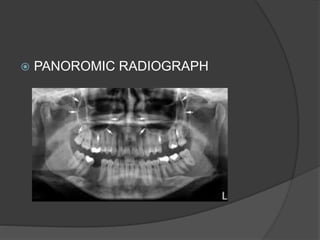

RADIOGRAPHS

 IOPA

 PANOROMIC RADIOGRAPH

 CT